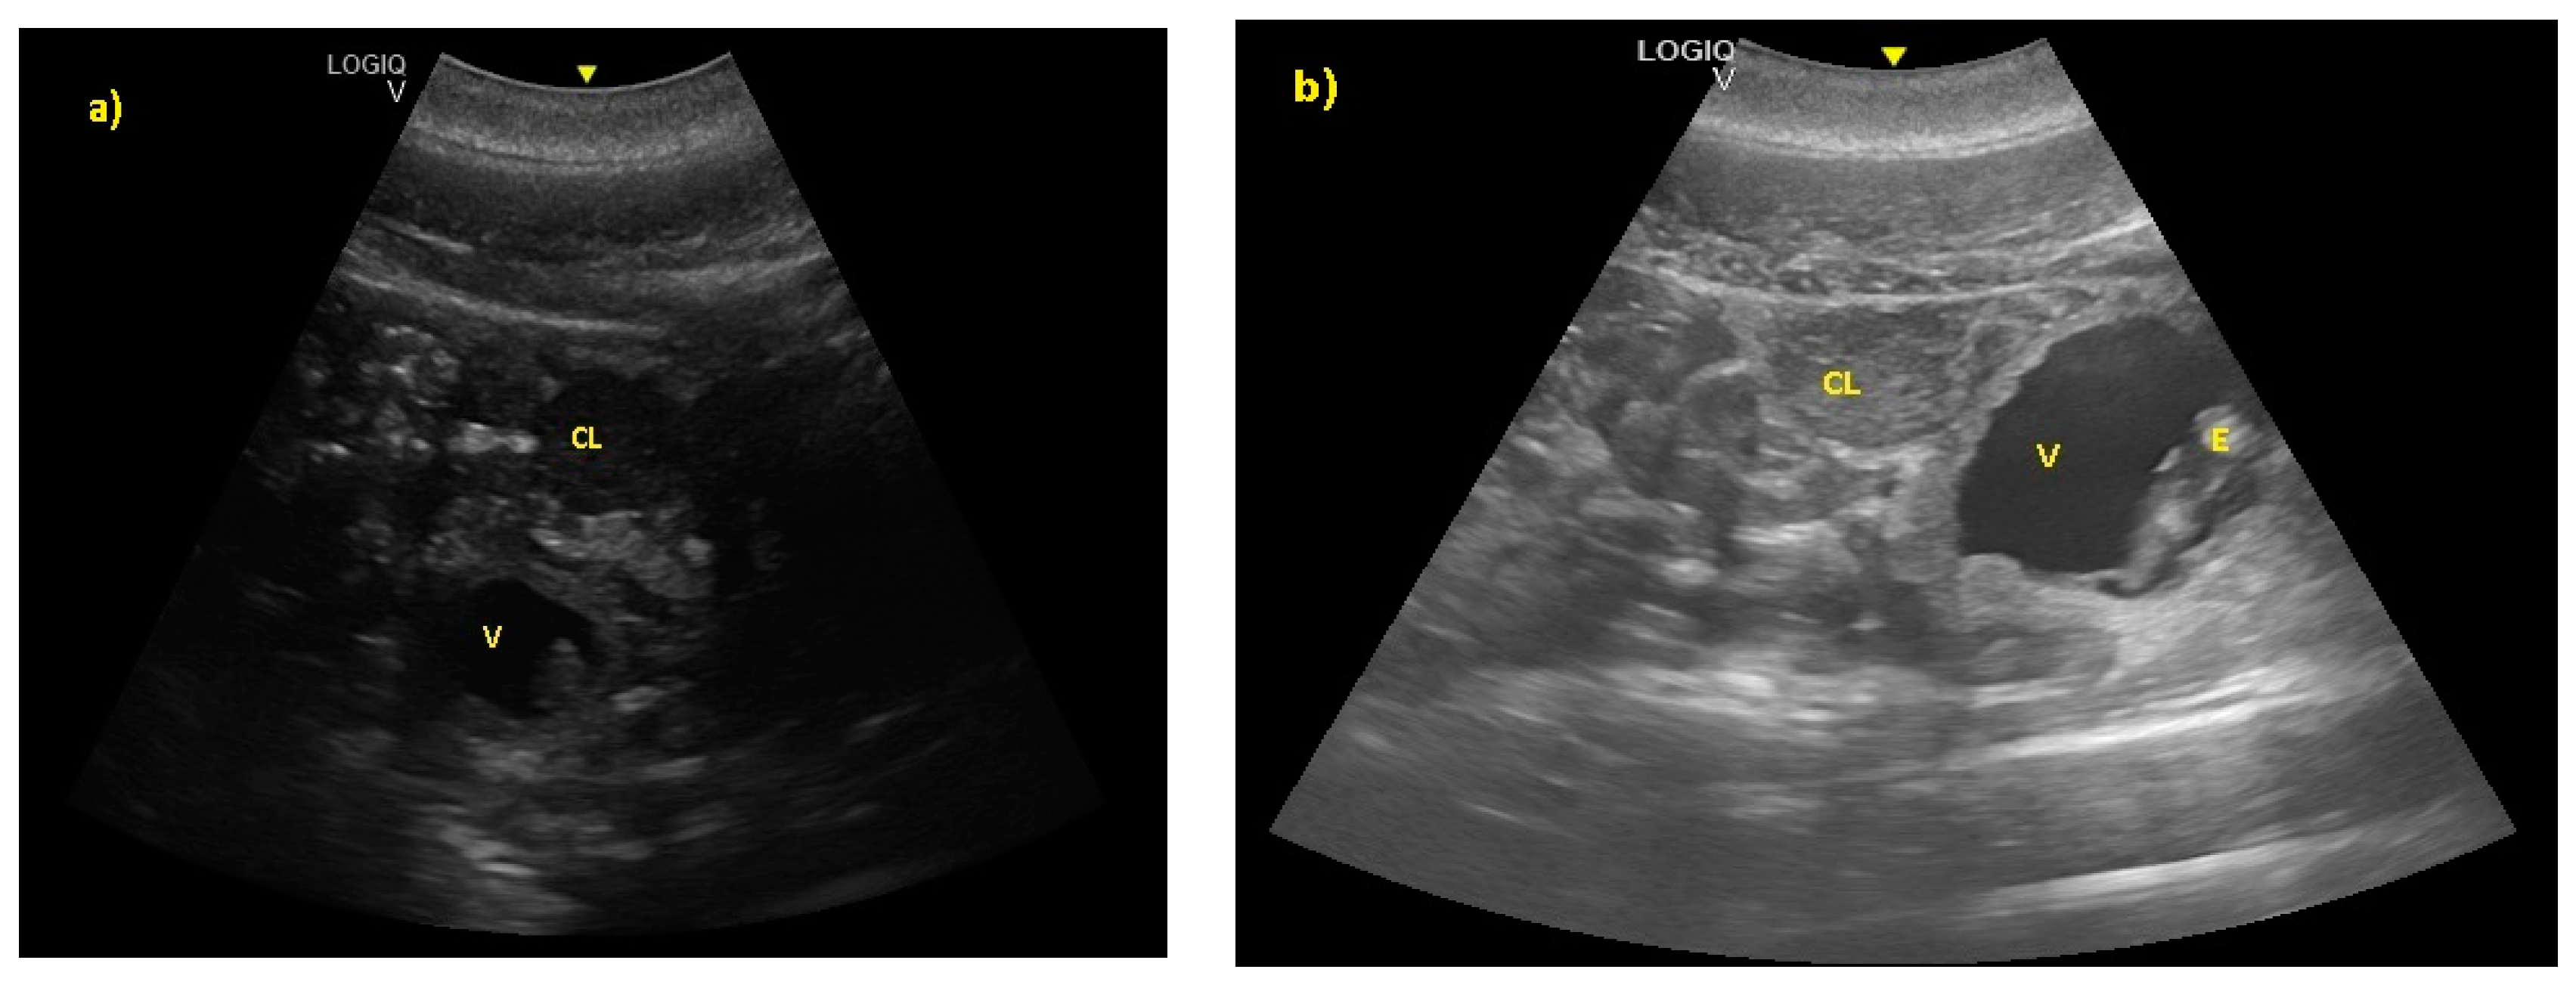

The embryonic vesicle was recognizable at 29 ± 3 days post-ovulation on the apex of the uterine horn as a roundish structure with an average diameter of 1.21 cm with an anechoic content. In the following week, it was possible to recognize the embryo inside it as an elongated hyperechoic structure (Figure 2).

Figure 2.

(a) The embryonic vesicle at 38 ± 2 days post-ovulation appeared as a roundish structure with an anechoic content and a hyper-echoic structure inside (V), under the CL. (b) At 52 ± 3 days, the embryo was perfectly recognizable (E).

The distinction between head and trunk was visible starting from 68 ± 5 days after ovulation. From the 216 ± 5 days of gestation, measurements started to be hard to realize with accuracy. In fact, in the evaluations after this last period, the position/orientation of the fetus and its size meant that it was not possible to take reliable measurements thereafter. Starting from 68 ± 5 days after ovulation, the embryonic cardiac mechanisms were displayed as a point of maximum fluctuation of the echoes. The heart rate was measured because the cardiac mechanics became visible and remained constant between 155 and 198 bpm until the ninth month of pregnancy (Figure 3). During the last 3 months, it stabilized at 140 bpm, to reach 85 ± 5 bpm in the last 2 weeks of gestation. The first abdominal organs to be visualized were the stomach and the urinary bladder (98 ± 3 and 110 ± 2 days of gestation, respectively), which appeared as distinct and anechoic cavities. It was also possible to recognize the eye as an anechoic cavitary structure (Figure 4).